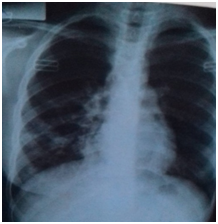

Female Patient (PT) 15 years old, referred to our hospital after more than 6 months of recurrent infections in right lower lobe (RLL) of the lung Figure A1 & A2. The PT had investigated, CXR was done Figure A3. The sputum was negative for TB many times. Bronchoscopy was done, no foreign body, no tumor, no anomalies, the washing was tested for TB and was negative. The decision for surgery was taken, the RLL was contracted, nodular and solid. RL Lobectomy was done. At second day post operation the PT had fever, sweat, no appetite and bad general condition. CXR revealed bilateral diffuse infiltrations. Figure B1. We decided to give her a trial TB treatment. After five days PT began to respond clinically. So TB treatment for minimum 6months is ordered.

B1 26-6-2019